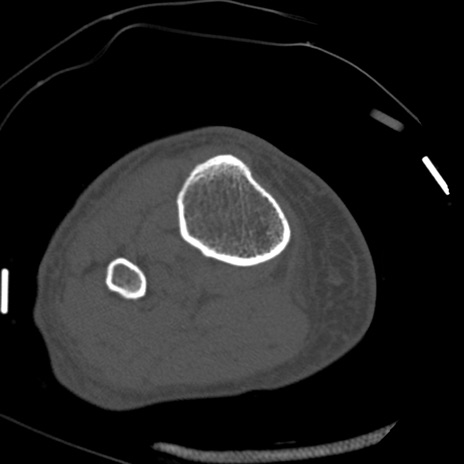

症例28 右膝関節CT(横断像)

右膝関節CT